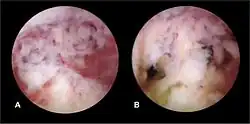

Hysteroscopic view of intrauterine adhesions

The history of a pregnancy event followed by a D&C leading to secondary amenorrhea or hypomenorrhea is typical. Hysteroscopy is the gold standard for diagnosis.[18] Imaging by sonohysterography or hysterosalpingography will reveal the extent of the scar formation. Ultrasound is not a reliable method of diagnosing Asherman's Syndrome. Hormone studies show normal levels consistent with reproductive function.

Fertility may sometimes be restored by the removal of adhesions, depending on the severity of the initial trauma and other individual patient factors. Operative hysteroscopy is used for visual inspection of the uterine cavity during adhesion dissection (adhesiolysis). However, hysteroscopy is yet to become a routine gynaecological procedure and only 15% of US gynecologists perform office hysteroscopy.[32] Adhesion dissection can be technically difficult and must be performed with care to not create new scars and further exacerbate the condition. In more severe cases, adjunctive measures such as laparoscopy are used in conjunction with hysteroscopy as a protective measure against uterine perforation. Microscissors are usually used to cut adhesions. Electrocauterization is not recommended.[33]